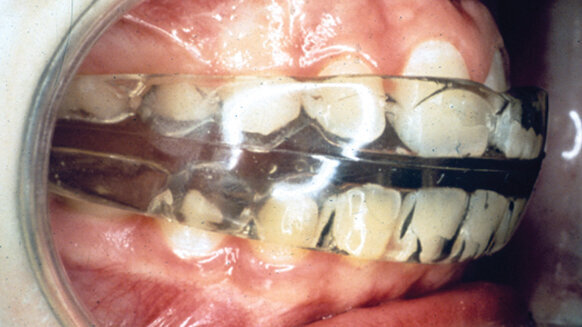

This procedure usually involves wearing a preformed appliance called Nite-Guide (Bergersen, 1995) only while sleeping to guide the erupting permanent teeth into an ideal occlusion. Usually two appliances are involved (Figs. 1a and 1b), and the second and last appliance serves as the retainer until about age 12. Once the permanent teeth erupt straight, the adult collagenous fibers form to stabilize them, which can prevent future relapse.